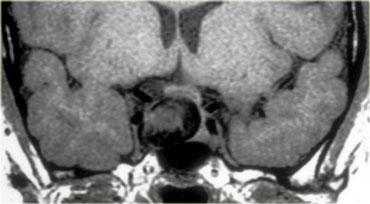

U Tuyến Yên Đại Tuyến (Macroadenoma)

Theo định nghĩa, u tuyến yên đại tuyến (macroadenoma) là các u tuyến có kích thước trên 10mm.

Chúng thường là các tổn thương đặc, mềm, thường có các vùng hoại tử hoặc xuất huyết khi kích thước tăng lên.

Khi phát triển, u trước tiên làm giãn rộng hố yên (sella turcica) rồi sau đó phát triển lên trên.

Trong ví dụ về u tuyến yên đại tuyến này, có sự lan rộng lên vùng trên yên (suprasellar) với sự đẩy lên và chèn ép giao thoa thị giác.

Do là các khối u mềm, chúng thường bị thắt lại tại màng hoành yên (diaphragma sellae), tạo nên hình ảnh ‘người tuyết’ đặc trưng.

Đây là một đặc điểm giúp phân biệt u tuyến yên đại tuyến với u màng não (meningioma).

Một đặc điểm khác có thể giúp phân biệt là sự giãn rộng của hố yên – điều này thường chỉ xảy ra với u tuyến yên đại tuyến có nguồn gốc từ trong hố yên.

Bên trái là một ví dụ khác về u tuyến yên đại tuyến.

Tổn thương bắt đầu từ hố yên, vốn đã bị giãn rộng, và lan rộng vào bể dịch não tủy trên yên (suprasellar cistern).

Lưu ý hình ảnh ‘người tuyết’ kinh điển được tạo ra do sự thắt nghẽn bởi màng hoành yên.

Chú ý mức dịch-máu (blood-fluid level), cho thấy có xuất huyết.